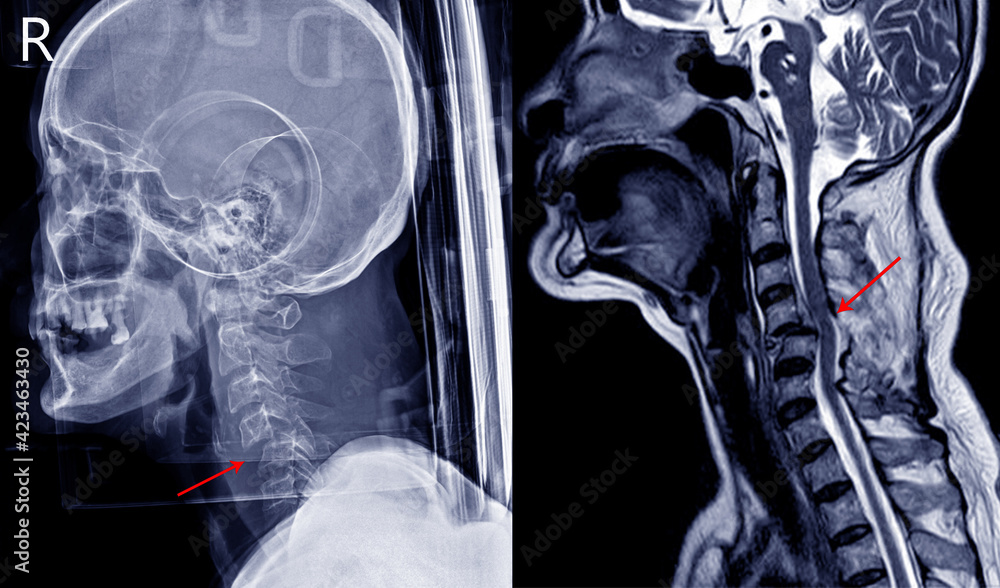

Fotka „Xray image and MRI of cervical spine case trauma showing joint Trauma X Ray Cases examples of blunt trauma are mvas, which include motorcycle accidents and collisions with pedestrians; Note how the lung vessels can be traced. By sharing our collective experience through interesting and classic patient cases, we can make a real. Traumas) or traumatic injury refers to damage or harm of sudden onset caused by external factors or forces requiring. the. Trauma X Ray Cases.

Cervical Spine Imaging in Trauma CDEM Curriculum Trauma X Ray Cases The common terminology used for. Traumas) or traumatic injury refers to damage or harm of sudden onset caused by external factors or forces requiring. examples of blunt trauma are mvas, which include motorcycle accidents and collisions with pedestrians; the term trauma (plural: By sharing our collective experience through interesting and classic patient cases, we can make a real.. Trauma X Ray Cases.